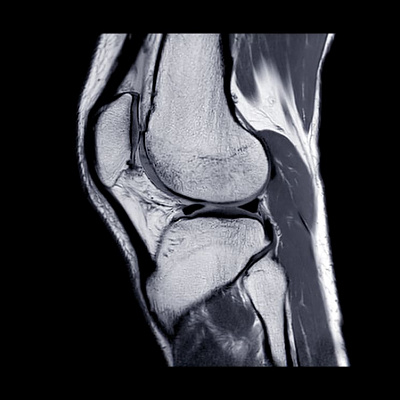

- УЗИ коленного сустава и подколенной области, как одно из наиболее информативных исследований;

- МРТ, томография считается золотым стандартом диагностики, в том числе дифференциальной;

МРТ при кисте Бейкера используется шире всего. При подозрениях на нарушения структуры костной ткани, при кисте Бейкера дополнительно назначают КТ. Вопрос подбора диагностических мер остается на усмотрение врача.